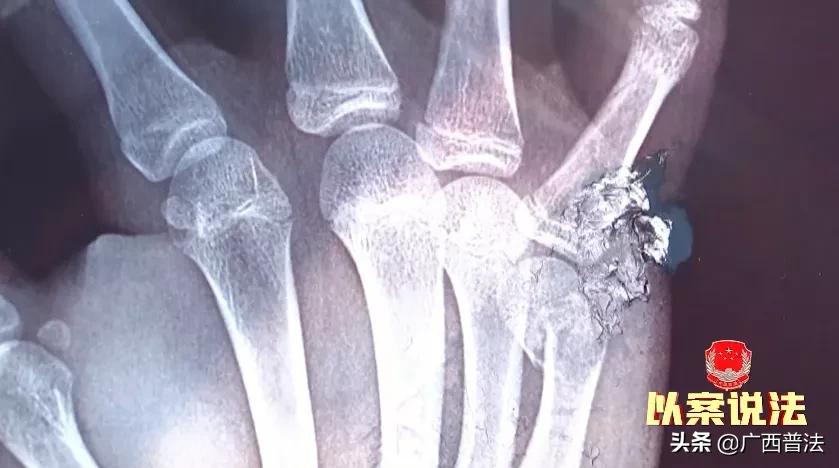

因为那个时间准备上学了,杨女士的儿子就开门出来,看见他还在那里咄咄逼人,后面手打到木板上小拇指骨折。杨女士说,当天下午,孩子的手越来越肿,也愈发的疼痛,杨女士赶紧把孩子送到医院就诊,结果被诊断为右侧第5掌骨远端骨折。